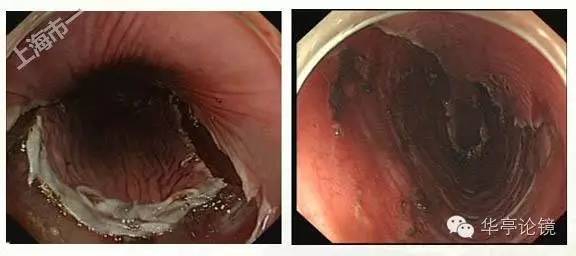

白光内镜:食管距门齿25-30cm见一浅表凹陷型病变,周边有颗粒状增生,病变粘膜粗糙、发红,分支血管网消失。提示食管IIc型病变。

碘染色:病变处粘膜大片脱染,环绕食管约1/3周径。EUS提示:病变区以粘膜层增厚为主,呈低回声改变,部分区域粘膜下层稍增厚,固有肌层完整,局部壁内可见小淋巴结。

ME--NBI内镜:IPCL为IV、V1型为主,散在少许局灶见V2、V3型改变,预测病变深度为m1为主。

白光内镜:距门齿25cm处食管后壁见片状粘膜浅表凹陷,病灶边缘可见局部隆起,病灶大小约2X1.5cm,提示食管IIc型病变。

碘染色:见病变区片状粘膜脱染。EUS:食道上段粘膜层增厚,累及部分粘膜下层,粘膜下层尚完整,与固有肌层分界清晰。局部壁内可见小淋巴结。

ME-NBI内镜:病变明显处分支血管网消失,IPCL呈IV-V1型改变为主,部分区域呈V2型改变。部分区域粘膜表层糜烂,表浅血管显露(绿色框内)。